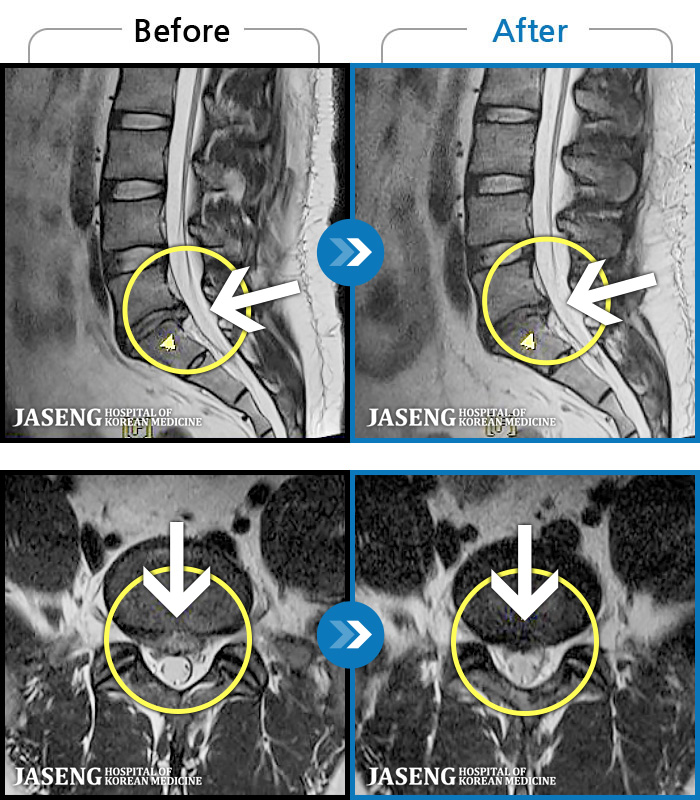

94 MRI ũ ʸ Ȯϼ.

㸮 ϻ .

[Ȼ] 23.03.13~24.05.08

ȯںп Ǹ ǿ ԿǾ, ο ġ ۿ Ƿ ġḦ Ͻñ ٶϴ.